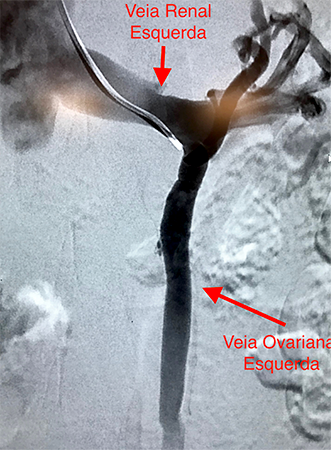

Embolização de Varizes Pélvicas

Varizes Pélvicas é o nome dado para a dilatação das veias localizadas no interior da pelve, próximas ao útero, bexiga e reto. Quando volumosas, essas varizes provocam dor no baixo ventre, dor durante a relação sexual, hemorroidas e varizes na face interna da coxa e períneo. Novas técnicas endovasculares pouco invasivas, permitem o tratamento do problema, com melhora na qualidade de vida desses pacientes.

A embolização de varizes pélvicas é feita através da punção de uma veia superficial do braço. Utilizando cateteres, o cirurgião vascular ocluirá os vasos doentes com liberação de espirais metálicas e substância química na forma de microespuma densa.

As molas em conjunto com a espuma provocarão a oclusão gradual das veias que originam as varizes, levando ao seu desaparecimento.